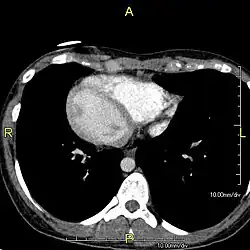

Situs inversus is found in about 0.01% of the population, or about 1 person in 10,000. In the most common situation, situs inversus totalis, it involves complete transposition (right to left reversal) of all of the viscera. The heart is not in its usual position in the left chest, but is on the right, a condition known as dextrocardia (lit. 'right-hearted'). Because the relationship between the organs is not changed, most people with situs inversus have no associated medical symptoms or complications.[1]

Effect on anatomy

The condition affects all major structures within the thorax and abdomen. Generally, the organs are simply transposed through the sagittal plane. The heart is located on the right side of the thorax, the stomach and spleen on the right side of the abdomen and the liver and gall bladder on the left side. The heart's normal right atrium occurs on the left, and the left atrium is on the right. The lung anatomy is reversed and the left lung has three lobes while the right lung has two lobes. The intestines and other internal structures are also reversed from the normal, and the blood vessels, nerves, and lymphatics are also transposed.

If the heart is swapped to the right side of the thorax, it is known as "situs inversus with dextrocardia" or "situs inversus totalis". If the heart remains on the normal left side of the thorax, a much rarer condition (1 in 2,000,000 of the general population), it is known as "situs inversus with levocardia" or "situs inversus incompletus".

Diagnosis of situs inversus can be made using imaging techniques such as x-ray, ultrasound, CT scan, and magnetic resonance imaging (MRI).[9]